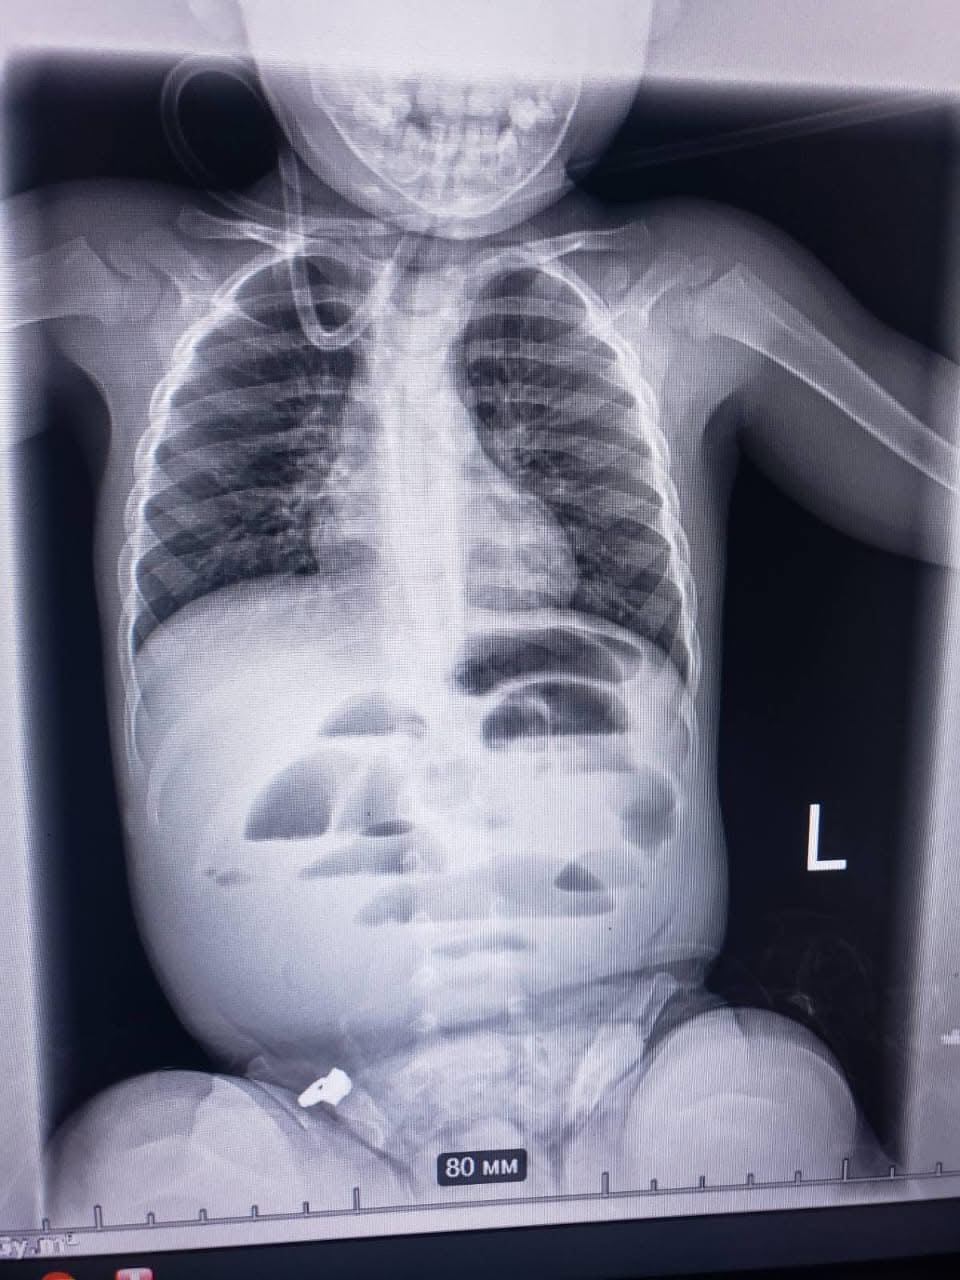

До «Регіонального медичного центру родинного здоров’я» було доставлено дитину віком 1 рік 8 місяців із підозрою на кишкову непрохідність. Під час рентгенологічного обстеження органів черевної порожнини лікарі виявили характерні ознаки непрохідності.

Мультидисциплінарна команда медиків прийняла рішення про термінову операцію. Під час хірургічного втручання у кишківнику було знайдено стороннє тіло, яке повністю перекривало його просвіт. Ним виявилася гідрогелева кулька діаметром близько 3 сантиметрів. Після видалення кульки та накладання швів дитину переведено до відділення інтенсивної терапії.